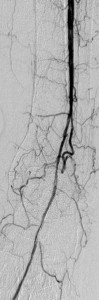

After instituting strategies to minimize contrast-induced nephropathy, I employed atherectomy of the distal LSFA and popliteal stenoses and angioplasty of the multifocal stenoses of her anterior tibial artery down to the dorsalis pedis artery to restore reasonable flow to her foot that helped the ulcer heal.

Images in the top panel illustrate her disease before the interventions, those in the middle panel illustrate some intraprocedural steps (balloon angioplasty), while those in the bottom panel illustrate improved blood flow to the foot following treatment.